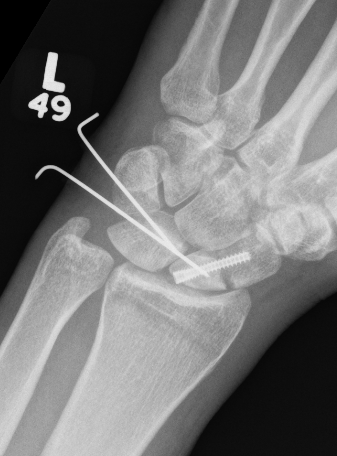

CT

Trans-scaphoid perilunate dislocation

Perilunate dislocation